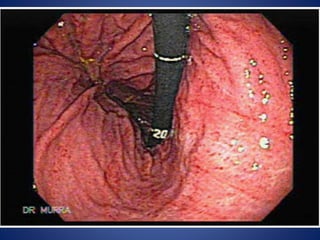

Peptic ulcer

• The term ‘peptic ulcer’ refers to an ulcer in the lower

esophagus, stomach, or duodenum.

• Pathology: An ulcer forms when there is an

imbalance between aggressive forces, i.e., the

digestive power of acid and pepsin, and defensive

factors i.e., the ability of the gastric and duodenal

mucosa to resist this digestive power. However, in

the majority of patients acid secretion is within

normal limits or is moderately raised. In these

individuals, damage to the gastric mucosal barrier is

necessary to facilitate the damaging effect of acid

and pepsin. The initial damage results from

Helicobacter pylori, NSAID’s, and smoking.